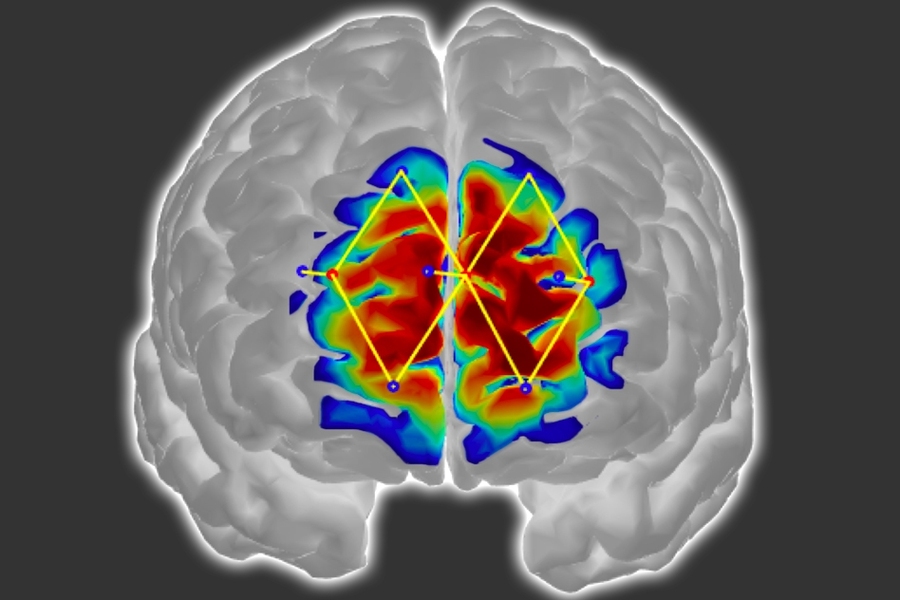

Presenting their findings at the International Conference on Affective Computing and Intelligent Interaction, the research team detailed their methodology for objectively measuring patient discomfort. Their approach utilizes an advanced neuroimaging technology known as functional near infrared spectroscopy (fNIRS), employing strategically positioned cranial sensors to detect oxygenated hemoglobin levels that serve as neural activity indicators.

The scientific team strategically positioned just a handful of fNIRS sensors on subjects' foreheads to monitor prefrontal cortex activity—a crucial region for pain perception and processing. Leveraging the captured neural data, researchers engineered customized machine learning algorithms designed to recognize distinctive patterns in oxygenated hemoglobin levels correlated with pain experiences. Once properly positioned, these sensor arrays can identify patient discomfort with an impressive 87% accuracy rate.

Conventional fNIRS methodologies typically require comprehensive sensor placement surrounding the patient's entire cranium. This technology operates by emitting various near-infrared light wavelengths through the skull into brain tissue. Oxygenated and deoxygenated hemoglobin molecules absorb these wavelengths differentially, creating distinctive signal modifications. As infrared signals reflect back toward the sensors, advanced processing algorithms analyze these modified wavelengths to quantify concentrations of each hemoglobin variant across different brain regions.

During painful experiences, brain regions associated with pain processing demonstrate significant increases in oxygenated hemoglobin alongside corresponding decreases in deoxygenated variants—changes readily detectable via fNIRS monitoring. However, traditional fNIRS implementations require extensive sensor arrays encircling the entire head, resulting in time-consuming setup procedures and considerable discomfort for bedridden patients. Furthermore, this comprehensive sensor arrangement proves impractical for individuals undergoing surgical procedures.

Consequently, the research team redesigned their fNIRS approach to exclusively capture signals originating from the prefrontal cortex. Although pain perception involves coordinated activity across multiple brain regions, scientific evidence demonstrates that the prefrontal cortex serves as the critical integration center for these distributed pain signals. This discovery enabled researchers to limit sensor placement exclusively to the forehead area.

Traditional fNIRS technologies face additional challenges related to signal contamination from extracranial sources such as skull and superficial tissue layers, introducing significant noise into measurements. To overcome this limitation, the research team incorporated supplementary sensors specifically designed to detect and eliminate these interfering signals.